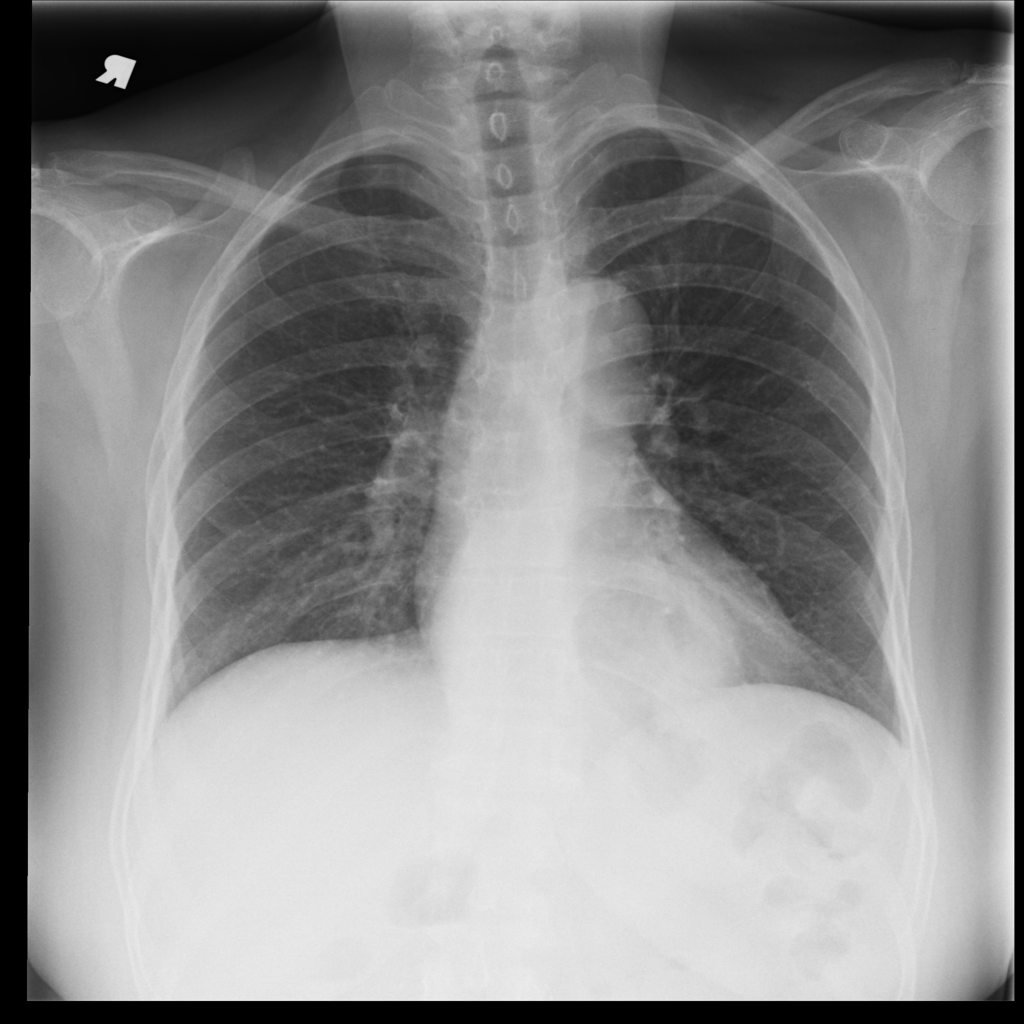

PAT-C048 · IMG-001Hernia

PAT-C048 · IMG-001

PA